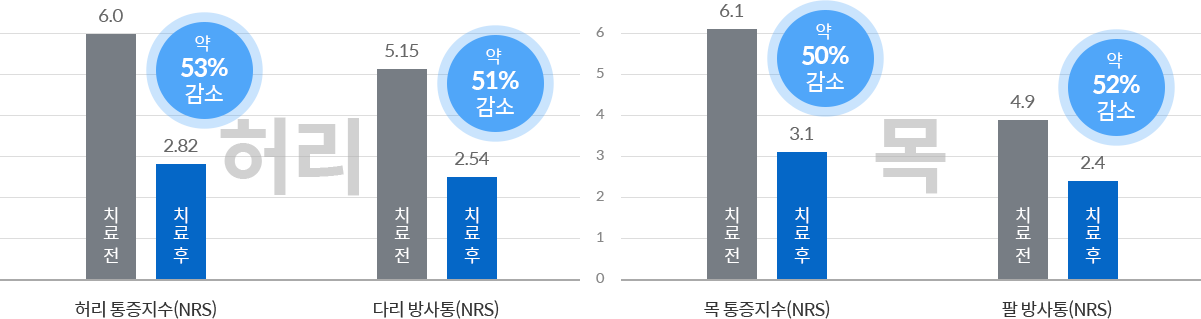

022주 입원집중치료를 통해 통증 50% 이상 감소

허리디스크* 평균입원 2~3주 기준

목디스크* 평균입원 2~3주 기준